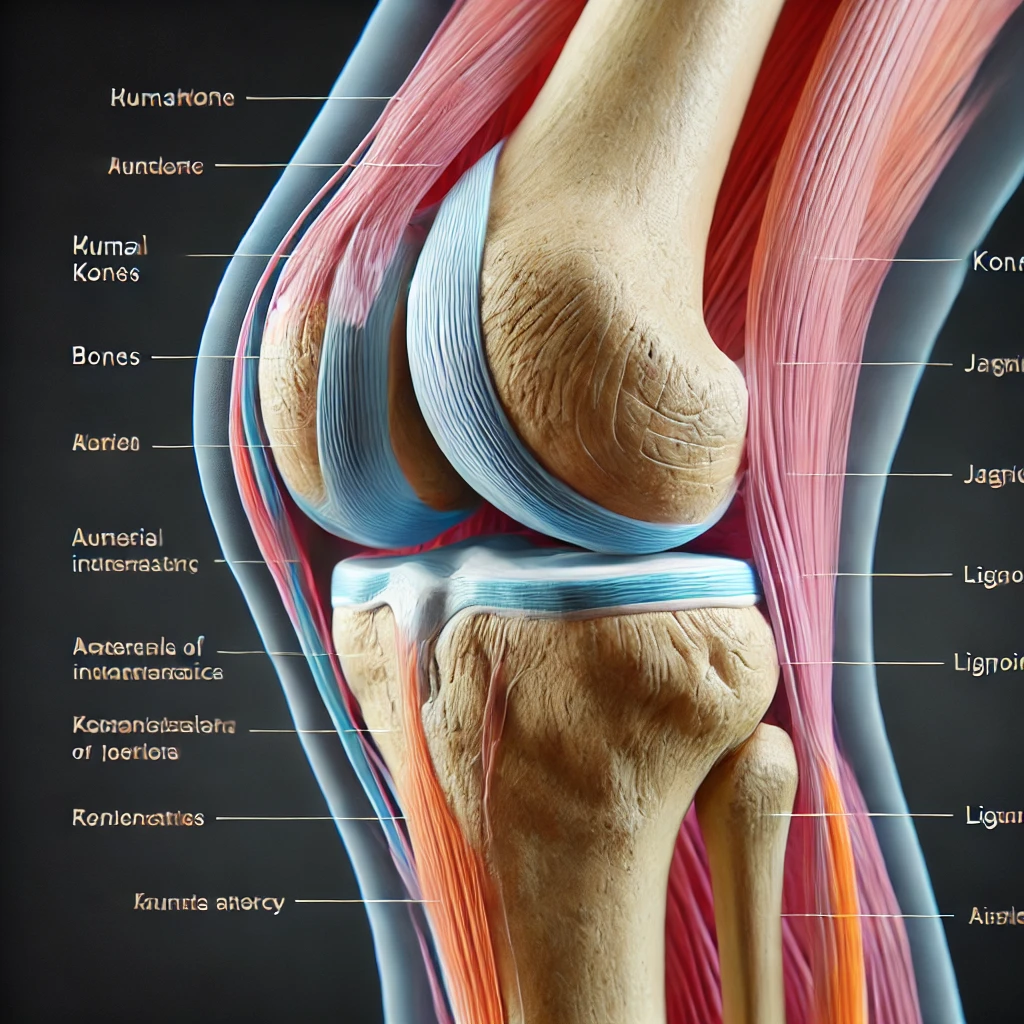

콘드로이친이란?

콘드로이친(Chondroitin)은 연골 조직의 주요 구성 성분 중 하나로, 주로 관절 건강을 지키는 데 중요한 역할을 합니다. 특히 나이가 들면서 연골이 손상되고 관절이 약해지는데, 이때 콘드로이친은 연골 조직의 회복을 촉진하고 염증을 억제하여 통증을 완화시켜 줍니다.